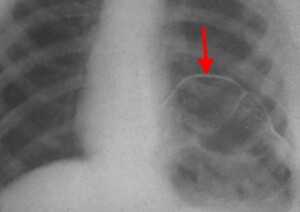

Рентген. Рентгенологическое исследование является решающим в диагностике релаксации, при этом определяются следующие симптомы:

- стойкое повышение уровня расположения соответствующего купола диафрагмы до 2 - 5 ребра;

- в горизонтальном положении диафрагма и прилежащие к ней органы брюшной полости смещаются кверху;

- контур диафрагмы представляет собой ровную, непрерывную дугообразную линию.

Нередко выявляется ателектаз нижних отделов легкого и смещение средостения.

Релаксация диафрагмы рентген (левый купол)